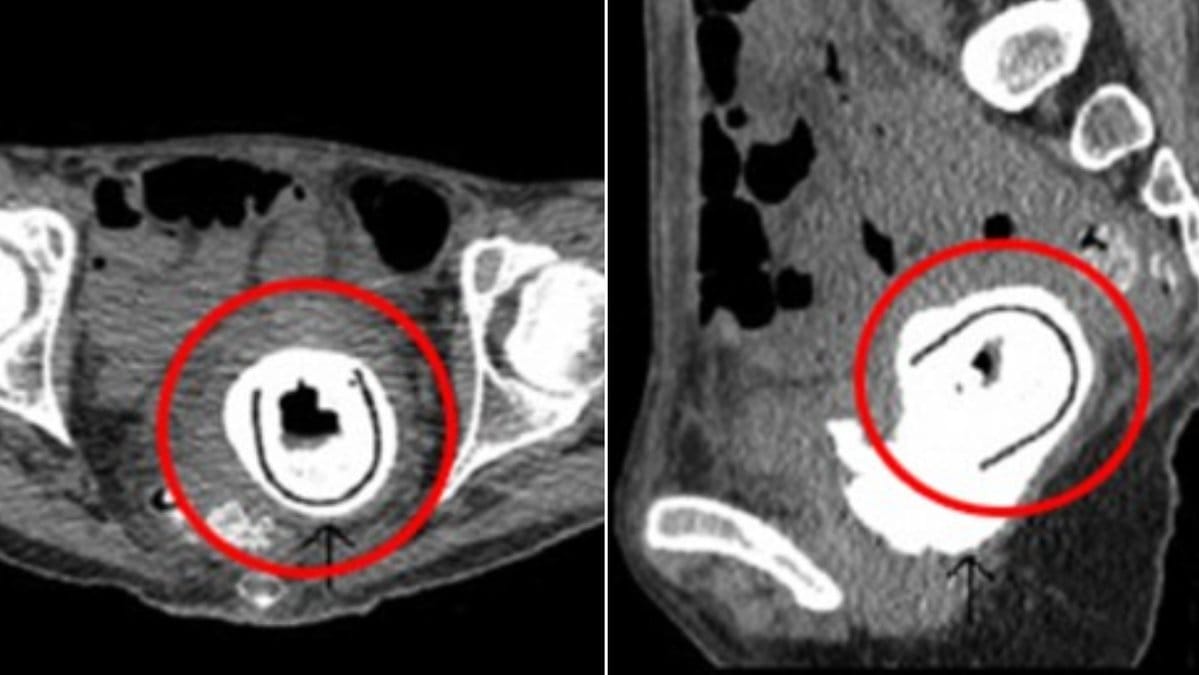

Läkarna som undersökte henne blev sedan ganska chockade när de insåg att hon hade ett föremål som fastnat mellan vaginan och urinblåsan, skriver Daily Mail och hänvisar till The Journal of Sexual Medicine.

När läkarna sen opererade bort den visade det sig vara en elva centimeter lång sexleksak – som kvinnan tillsammas med sin partner hade använt hela tio år tidigare. Kvinnan berättade också, enligt Daily Mail, att hon hade varit berusad under användningen och att hon inte kommer ihåg huruvida hon tog ut den eller inte.